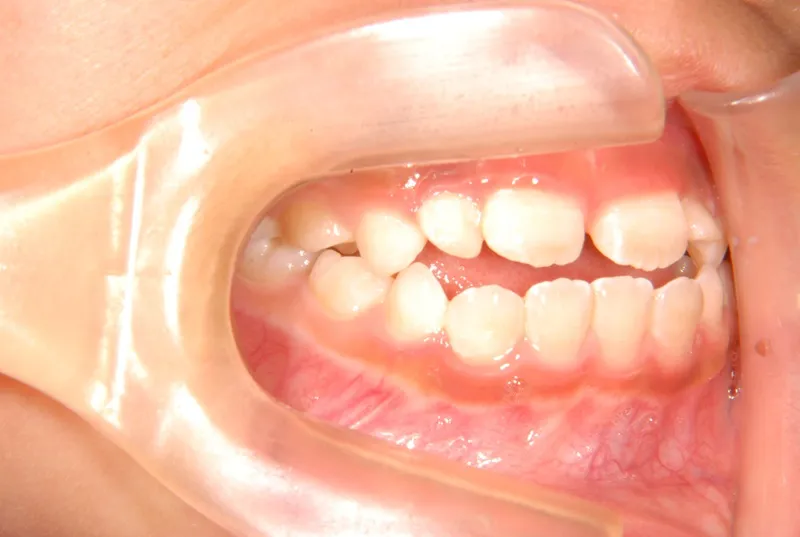

【子供の矯正(一期)】叢生・開咬・前歯で噛めない・舌癖・7歳女児【M.O様】

初診時年齢 小学校1年生 (女性) 主訴 前歯で噛めない

診断名 叢生・開咬 装置名

拡大床

状態 永久歯が生える隙間がない(叢生)

前歯で噛めない(開咬/オープンバイト)

舌の癖によって下の前歯が出て、上の前歯が短いです。

取り外し式の装置で上下の歯並びを拡げて、下の前歯を引っ込めます。

初診